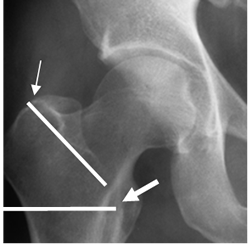

Fig 52. Clasificación de fractura extracapsular.

Rx AP. Fractura intertrocantérica (Flecha delgada) y subtrocantérica (Flecha gruesa).